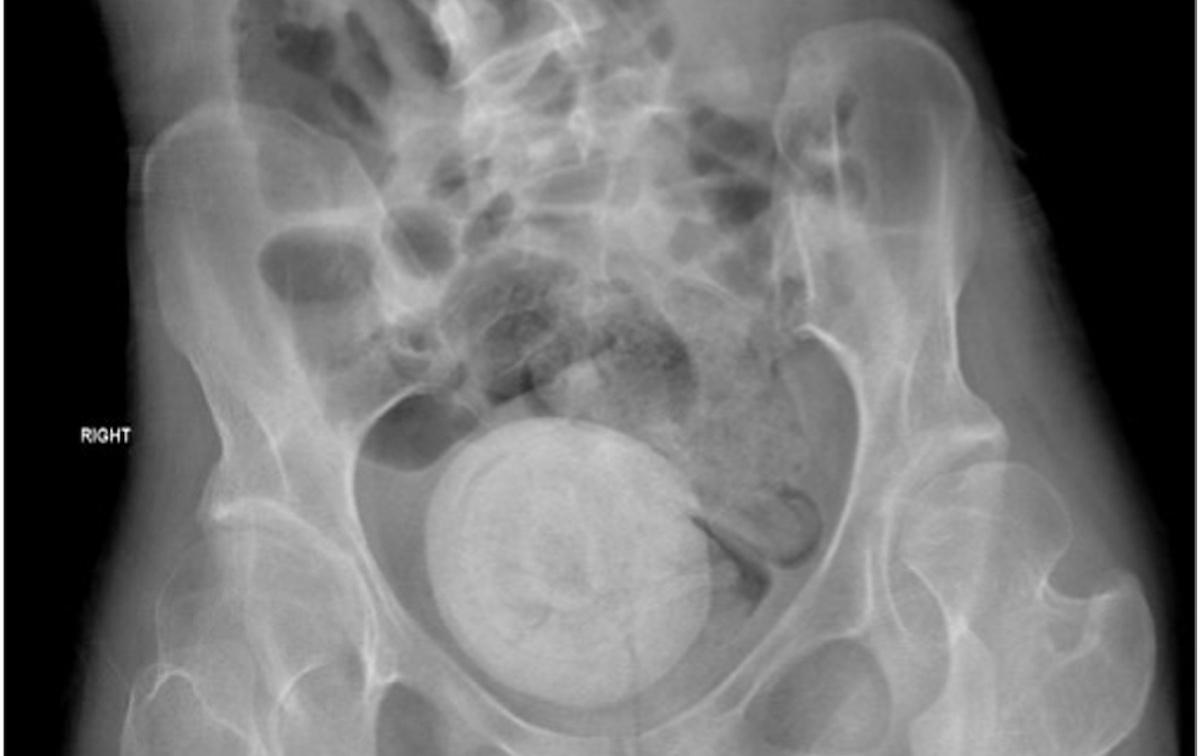

Dans le cas de cette patiente, les médecins ont réalisé un scanner pelvien et abdominal après son arrivée aux urgences. Cela leur a permis de découvrir une masse importante, de forme ronde, dans la zone pelvienne. "Le scanner de l'abdomen et du bassin a montré une structure ronde calcifiée dans le bassin occupant l'espace entre la vessie et le rectum poussant probablement vers le haut de l'utérus occupant l'espace vaginal, décrivent-ils. Il mesure 9 × 10 cm ; un autre calcul obstructif de 1,4 cm a été observé."